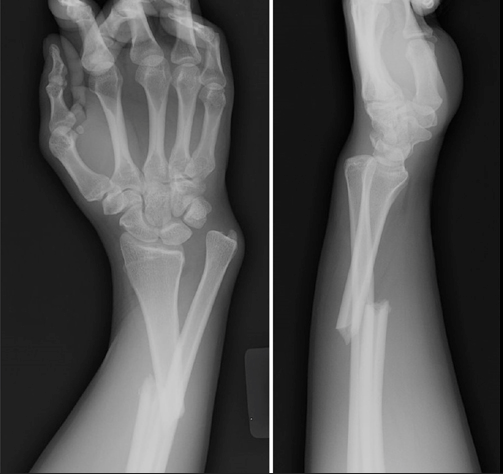

Name of this fracture.

What is a Galeazzi fracture?

Name of this injury.

What is a lunate dislocation?